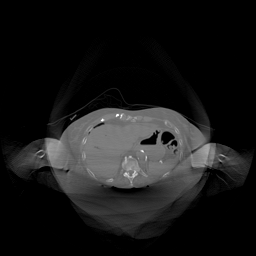

The results for simulated noisy data are shown in Fig. 2. The first and third rows display two representative slices from the test set, and the second and fourth rows present the corresponding error maps. The traditional WCE method suppresses cupping artifacts and recovers some missing anatomical structures but still shows noticeable deviations from the ground truth. Predictions from the four diffusion-based models demonstrate a markedly improved ability to restore anatomical structures. Among them, cDDPM fails to fully reconstruct the patient bed and retains residual noise in its outputs. This noise is attributable to an incomplete reverse denoising process rather than residual Poisson noise, as evidenced in our noise-free experiments (Fig. 5 in the Appendix). PatchDiffusion, diffusionGAN, and I2SB achieve similar visual quality, with I2SB producing the cleanest and most consistent reconstructions.

The experimental results on clinical head data are shown in Fig. 4. The reference images were reconstructed using the fast iterative shrinkage-thresholding algorithm (FISTA) with total variation regularization from non-truncated projection data. In the WCE reconstructions (Fig. 4(b)), severe truncation prevents accurate recovery of anatomical structures outside the FOV. Despite being trained solely on simulated data with a domain gap, all deep learning models can restore a substantial portion of the missing anatomy. Among them, the diffusion-based methods recover soft-tissue boundaries more faithfully than the conventional deep learning approach FBPConvNet, highlighting their stronger image generation capability. However, cDDPM reconstructions exhibit more noticeable noise than those from other methods, consistent with the simulated data results. The patchDiffusion model introduces artifacts within the FOV, likely due to its patch-wise processing strategy. While I2SB shares the same limitations as other diffusion models in perfectly restoring soft-tissue detail, it produces fewer residual noise patterns and fewer artifacts within the FOV boundaries. Overall, Fig. 4 demonstrates the strong efficacy of I2SB in reconstructing real CBCT data.